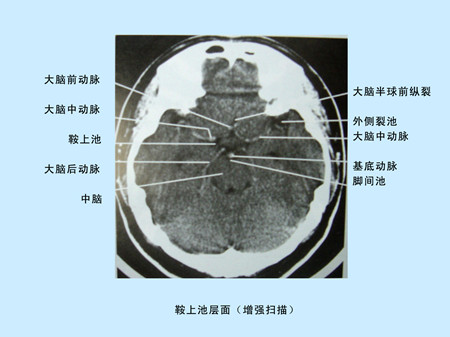

CT(Computed Tomography)是電子計算機X射線斷層掃描技術簡稱。CT的工作程序是這樣的:它根據人體不同組織對X線的吸收與透過率的不同,將測量所獲取的數據輸入電子計算機,電子計算機對數據進行處理后,攝下人體被檢查部位的斷面或立體的圖像,可發現體內任何部位的細小病變。CT圖像是重建圖像。

CT由于它的特殊價值,已廣泛應用于臨床。但CT設備比較昂貴,檢查費用偏高,某些部位的檢查,價值,尤其是定性,還有一定限度,所以不宜將CT檢查視為常規手段,應在了解其優勢的基礎上,合理的。在頭部檢查中,CT可用于腦出血,腦梗塞,動脈瘤,血管畸形,各種腫瘤,外傷,骨折,先天畸形等方面的。

超聲經顱多普勒(TCD)儀與CT的區別

1)超聲經顱多普勒(TCD)儀提供的是實時動態的腦血管的血流動力學資料。

2)CT提供的是大腦實質細胞的損壞與形態學上改變的影像學資料 。

CT平掃及增強掃描腦組織圖像顯示                                                       超聲經顱多普勒檢測時顯示圖像